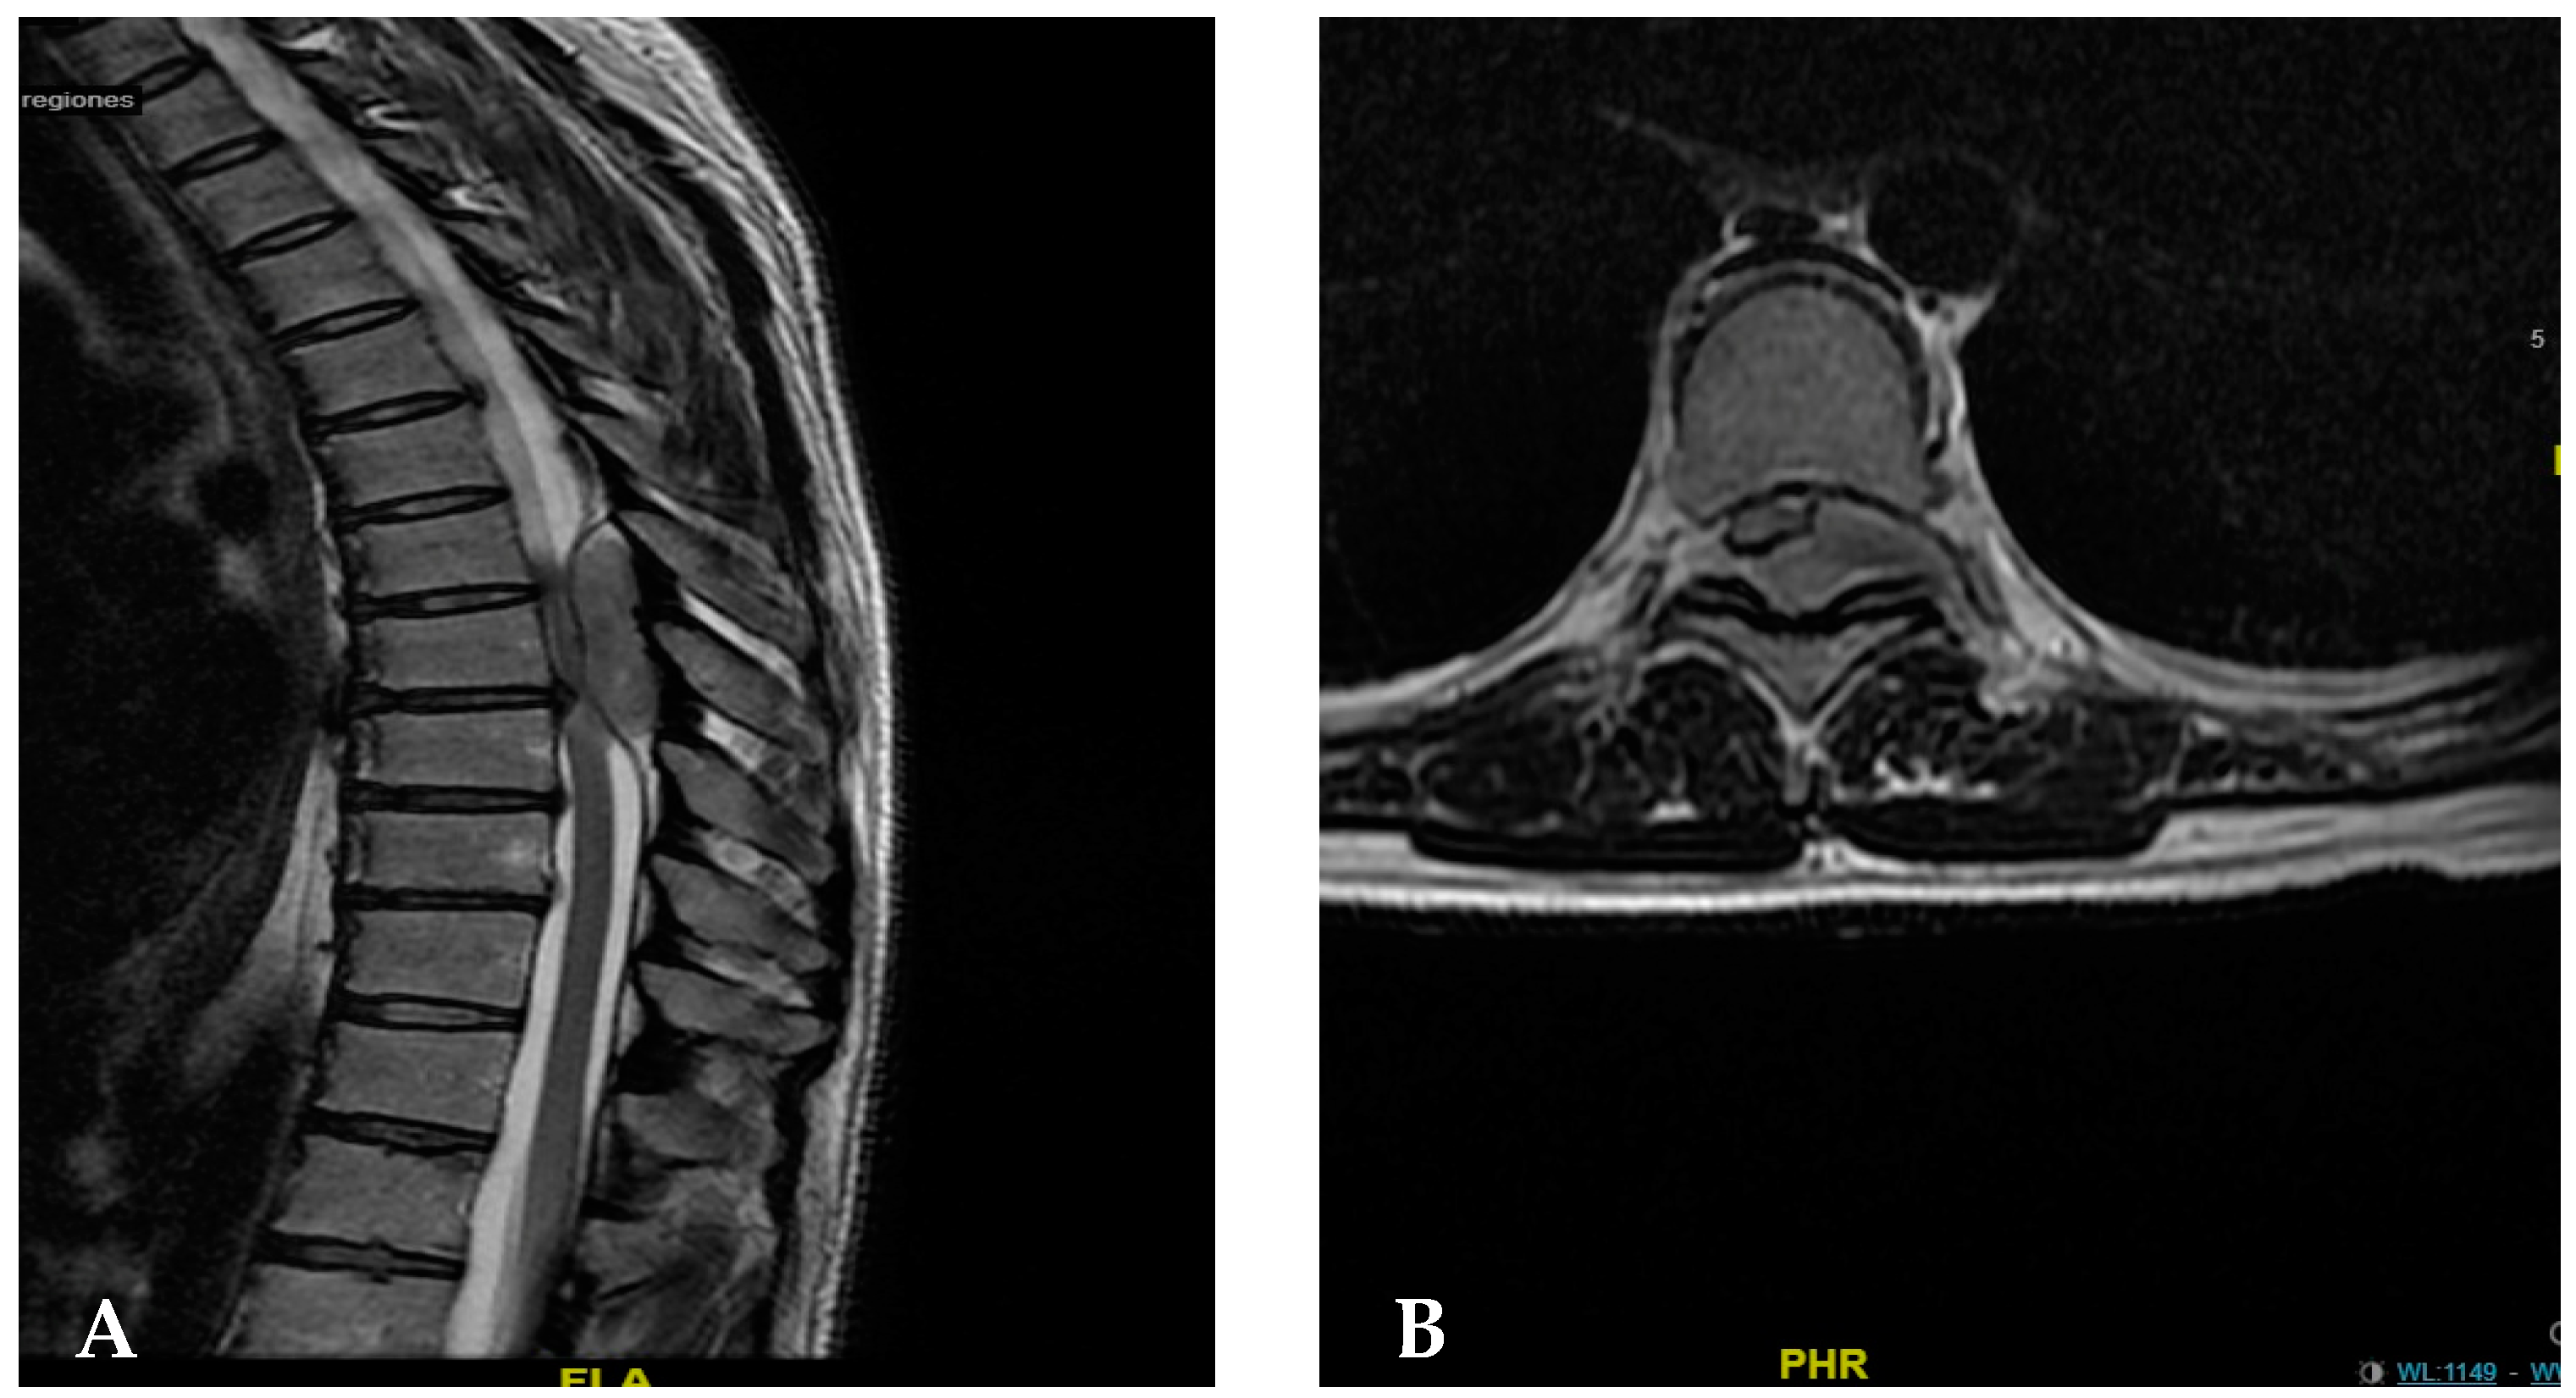

2. Case Presentation